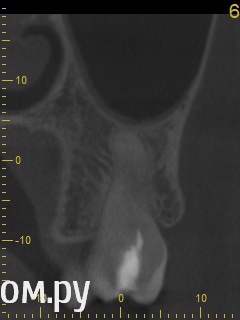

red_butler Опубликовано 21 апреля, 2014 Поделиться Опубликовано 21 апреля, 2014 Снимок во время лечения делали? Коффердам и оптика использовались? На кт в тех срезах что Вы выложили кисты не вижу Ссылка на комментарий

Гарриевич Опубликовано 21 апреля, 2014 Поделиться Опубликовано 21 апреля, 2014 Кисты по снимкам нет. Удалять зуб ,по снимкам, причин нет Ссылка на комментарий

DmitrySH Опубликовано 21 апреля, 2014 Поделиться Опубликовано 21 апреля, 2014 Аналогично, никаких признаков воспаления в костной ткани вокруг зуба не увидел. Ссылка на комментарий

ромашечка Опубликовано 21 апреля, 2014 Поделиться Опубликовано 21 апреля, 2014 (изменено) Месяц хождения с гидроокисью кальция на воде никакого эфекта не дали. Зуб все еще под временной пломбой В каналах всё ещё гидроокись?? даже залезла за апекс?? Зачем? При третьем посещении врач констатировала что каналы чистые. Никаких признаков инфекции нет. И белезненная перкуссия от чего то другого. Специально проводила ревизию каналов при втором и третьем посещении без анастезии что бы понять где болит. Может у меня пробелы какие- но я не понимаю такой тактики. Болезненная перкуссия вполне может быть от того что каналы пустые или временно запломбированнны. Но мой взгляд , дотаточно качественно запломбировать ПОСТОЯННО каналы и проблема должна исчезнуть. Кисты не вижу. Изменено 21 апреля, 2014 пользователем ромашечка 1 Ссылка на комментарий